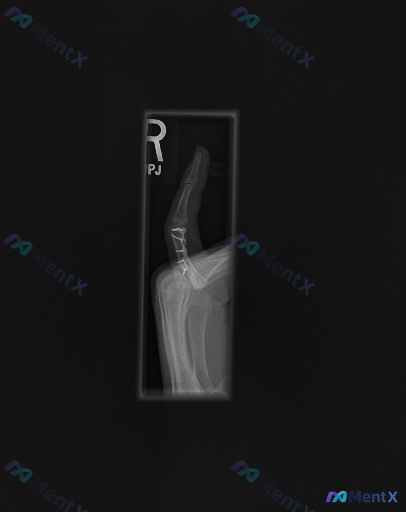

影像里明确能看到的:

- 近节指骨基底部至体部,有金属内固定物(多枚螺钉+微型钢板)

- 内固定范围内骨折线模糊,骨皮质连续

- 近侧、远侧指间关节间隙清晰,对合良好

- 局部软组织没有明显严重肿胀

影像报告的初步结论是“内固定在位,骨折处于愈合期”。

但这份资料的开头,直接标了一行:“存在异常”。